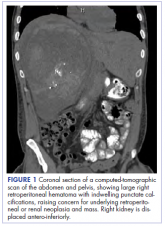

ArticlePrimary renal synovial sarcoma – a diagnostic dilemmaAuthor:Yellala et alPublish date: October 28, 2018 Read More